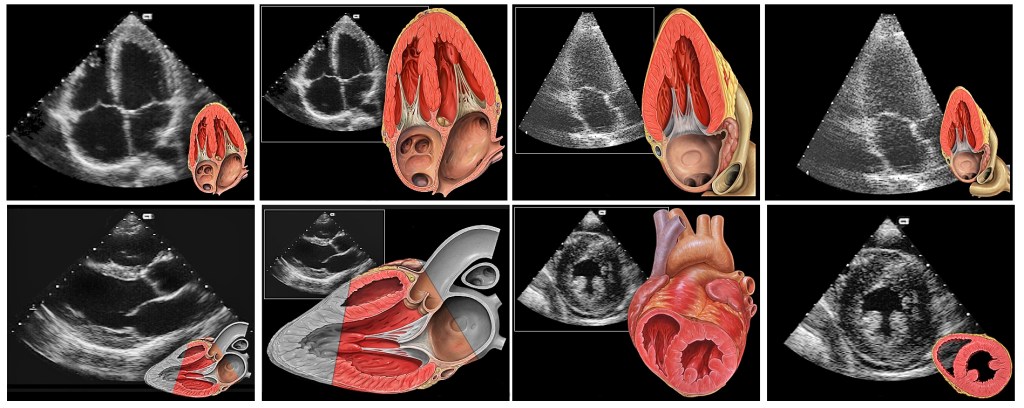

ASE Guidelines for Performing a Complete TTE